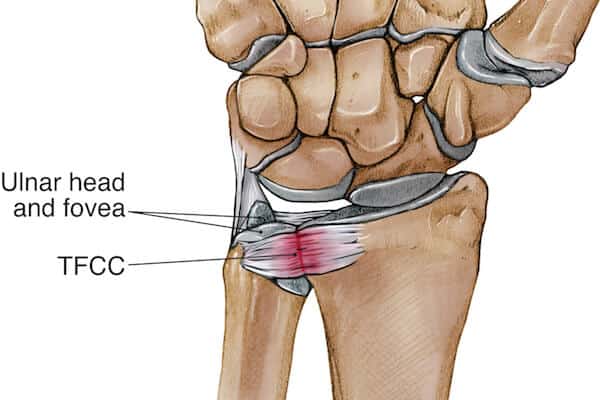

What is TFCC?

The Triangular Fibrocartilage Complex (TFCC) is a group of ligaments, cartilage, and connective tissue located on the small finger side of the wrist, stabilising the wrist and supporting load transmission between the forearm and hand. The TFCC acts as a shock absorber and stabiliser during gripping, twisting, and weight-bearing activities.

TFCC injuries can result from trauma, repetitive stress, or degenerative changes and are a common cause of ulnar or little finger sided wrist pain. The injury may involve tearing or degeneration of the cartilage or supporting ligaments and can affect daily hand function significantly if left untreated.